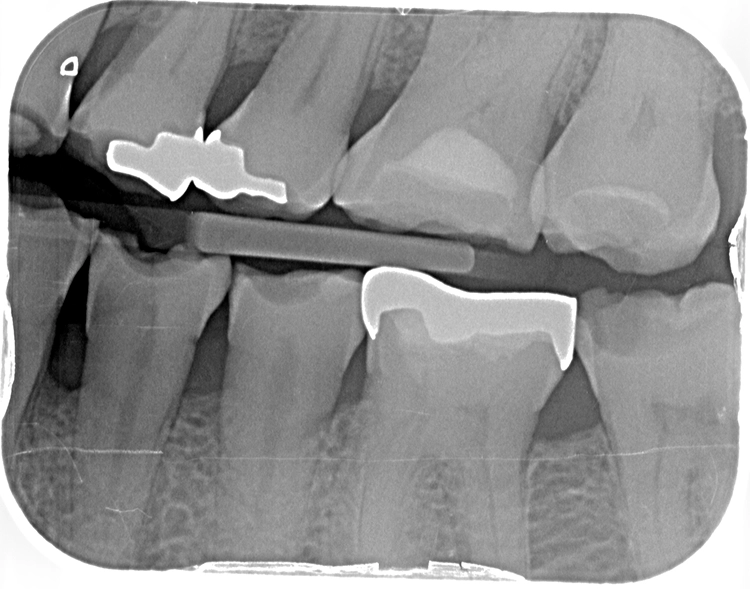

Die OPT-Aufnahmen zeigen keinen Anhalt auf nicht zahnverursachte Prozesse, dafür einen leichten bis mäßigen horizontalen und vertikalen Knochenabbau im Oberkieferseitenzahnbereich und generalisiert im Unterkiefer sowie einen periimplantären Knochenabbau in Regio 47 (Abb. 2). Die Zahnhartsubstanzdefekte imponieren als halbmondförmige Aufhellungen im Okklusalbereich von den Zähnen 37, 35, 34, 44 und 45. Es zeigen sich ebenso Aufhellungen im Approximalbereich mesial 24, distal 43 und mesial 37 (Abb. 4 und 5).

Die Zähne im Unterkiefer wurden unter Leitungsanästhesie (Articain 1:100.000, Aventis) und Zuhilfenahme einer Lupenbrille (4,5-fache Vergrößerung, Zeiss) präpariert (Abb. 17 und 18). Mittels Doppelfadentechnik erfolgte eine zweifache Abdrucknahme der präparierten Zähne: Einbringen eines ersten, getränkten (Racestyptine solution, Septodont) Fadens (Ultrapak 0, Ultradent), über welchen ein zweiter getränkter Faden größeren Durchmessers gelegt wurde (Ultrapak 1, Ultradent).